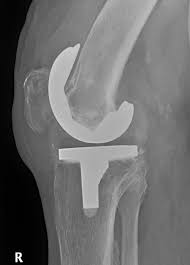

The company ORTHOPEDIC NIKIFOROV was founded in 1998 by the candidate of medical sciences. doctor of orthopedic-traumatologist of the highest category Nikiforov IA Owing to high professionalism and results of work, ORTONIC has gained well-deserved reputation and reputation among colleagues and population of Dnepropetrovsk region and CIS countries (Russia, Moldova, Armenia, etc.). The principle of the enterprise is NO IMPOSSIBLE, it is based on knowledge, experience and active implementation of modern technologies in orthopedics and traumatology. Conservative methods of treatment include individual selection of medicines, therapeutic blockades, manual therapy, massage, physiotherapy (vibration table, magnetotherapy, bioptron, electromyostimulation, etc.), rehabilitation with the suggestion of the necessary concomitant devices and means for the fastest recovery (corsets, bandages, various joint fixators, crutches, walking sticks, etc.). Various minor invasive interventions (chymonucleolysis, vertebroplasty, kyphoplasty, percutaneous nucleoplasty using cold plasma) that are performed on an outpatient basis are successfully used to treat problems associated with spine pathology. The latest modern treatment methods introduced in our company are endoscopic operations using the TYSSES technique of Joimax (Germany) with intervertebral hernias, stenosis and other pathologies of the spine, which allow to avoid complications occurring during open operations and the accompanying general anesthesia. We have many years of successful experience in traditional and modern minimally invasive endoprosthetics of large and small joints, which remains the main direction of our activity. Our company is the exclusive representative of the German company IO International Orthopaedics Holding GmbH, which based on the already known prostheses, its ideas and technological capabilities, has developed and implemented a new concept in hip replacement - an artificial joint prosthesis (ICON). We assist interested colleagues in training the operative technique for installing an artificial joint prosthesis - ICON, both in the workplace and in Germany. For 20 years we have been successfully cooperating with Sanitatshaus Gerd Klinz ortho team, an enterprise that for 20 years has been one of the leading places in Germany for the production of functional prostheses of the upper and lower limbs, as well as cosmetic prostheses of limbs and other body parts (nose, ears, eyeballs, fingers). We have an atmosphere of friendliness and human participation. Politeness, benevolence, the desire to understand and help is the basis of our attitude towards patients. We are always glad to see you and will do our best to make you feel great! We are waiting for you at: Ukraine, Dnepr, Gagarin Ave., 13 (under reconstruction) on all questions to address: tel .: +38 (050) 488-88-92 E-mail: orthonik.ukr@gmail.com Germany, Spine Nano Klinik, Zeppelinstr. 21, Potsdam Tel. +4901801121919 E-mail: kmw.nikiforov@hotmail.de